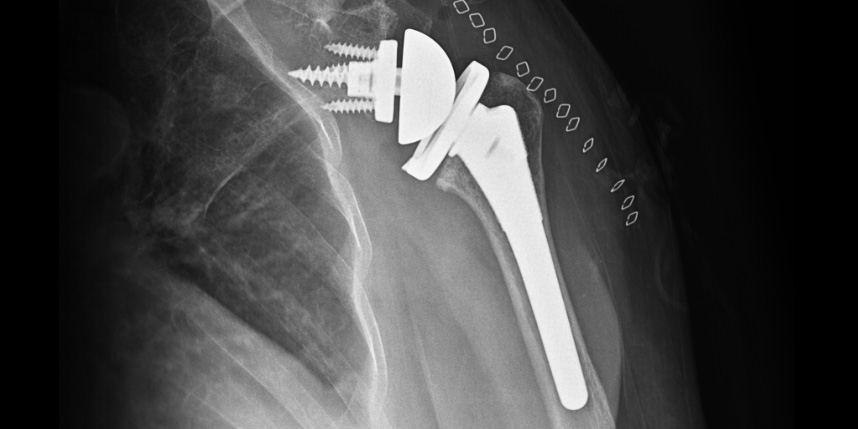

삼하게 망가져 거의 기능이 없는 관절을 제거한 후 특수하게 제작된 인공관절을 삽입하는 수술

역행성 인공관절 전치환술

역행성 인공관절 진치환술

(회전근개 심한 파열 및 관절염 진행)

* 환자에게 받은 소중한 자료입니다.